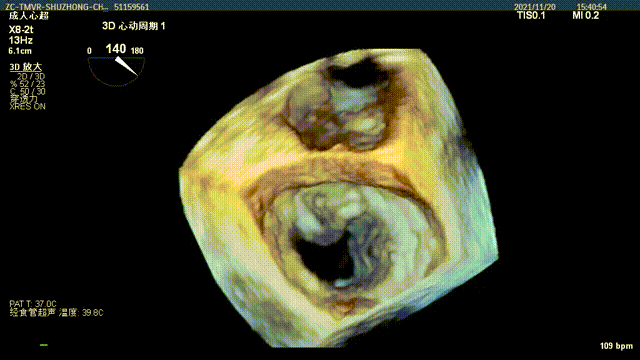

术前二尖瓣重度反流

人工二尖瓣启闭良好